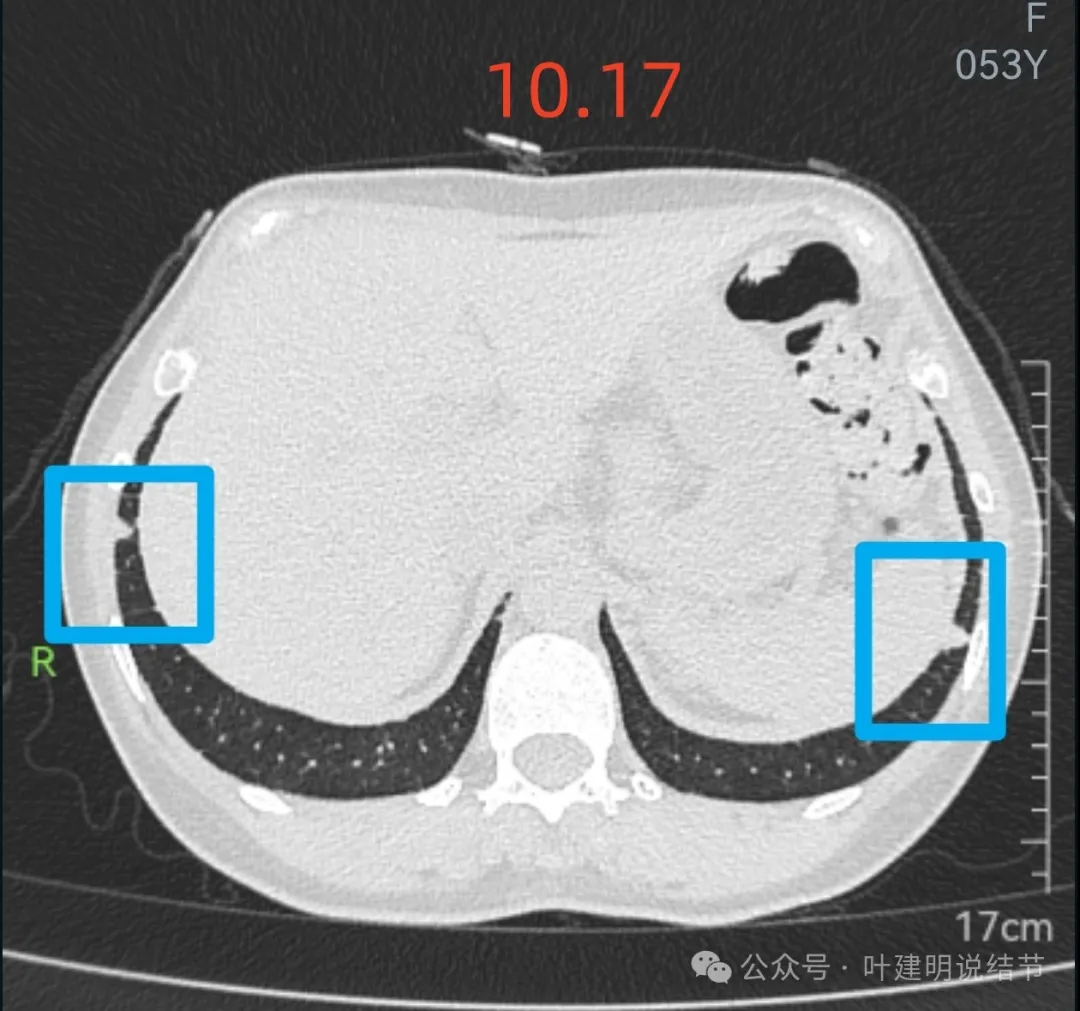

右下叶以及左下叶实性结节,缺乏膨胀性,没有收缩力,紧贴胸壁或膈肌无牵拉凹陷。

蓝色的是实性的小结节,缺乏膨胀性,两次检查都有,没有变化,考虑是良性的;红色的这些事10月份检查新增的,这两处比较明显的9月份的时候就是绿色框起来这个区域,当时是没有的。短时间内出现、多发病灶、边缘模糊、轮廓欠清,没有恶性特征,与炎性病变符合。建议查查隐球菌方面的化验,如此结果阳性,请呼吸内科或感染科处理。意见供参考!

上图就是236层面,报告说的结节主要的是指左下这处实性的。